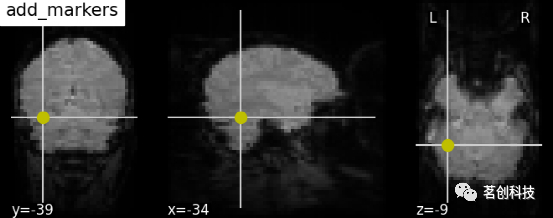

display.add_markers(coords, marker_color=' y ', marker_size=100):添加标记。

display = plotting.plot_anat(mean_haxby_img, title="add_markers",

cut_coords=[-34, -39, -9])

coords = [(-34, -39, -9)]

display.add_markers(coords, marker_color='y', marker_size=100)